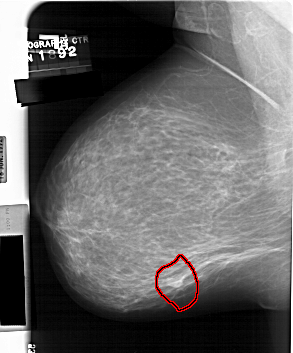

A_1560_1.LEFT_CC

LEFT_CC LINES 6871 PIXELS_PER_LINE 4906 BITS_PER_PIXEL 12 RESOLUTION 43.5 OVERLAY

FILE: A_1560_1.LEFT_CC.OVERLAY

TOTAL_ABNORMALITIES 1

ABNORMALITY 1

LESION_TYPE MASS SHAPE LOBULATED MARGINS OBSCURED

ASSESSMENT 4

SUBTLETY 4

PATHOLOGY BENIGN

TOTAL_OUTLINES 1

BOUNDARY